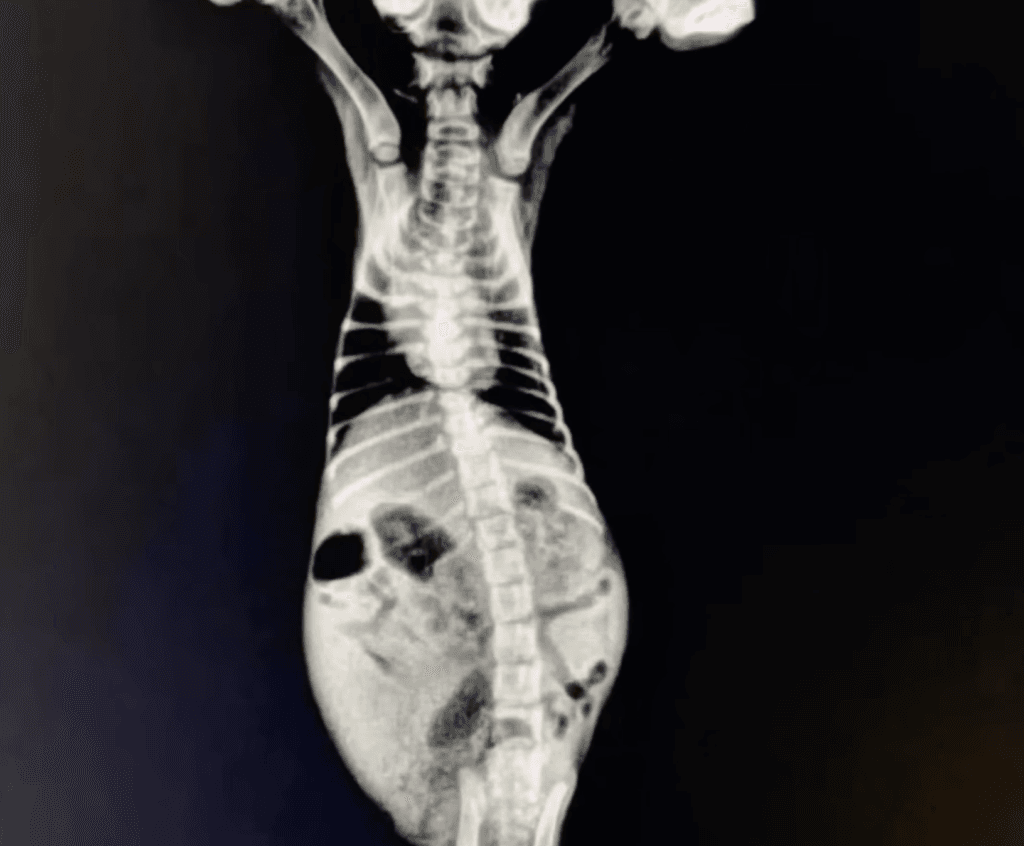

Tests revealed severe infections in both eyes and nose, and the prognosis was uncertain.

Gray soon noticed one of Jiu’s hind legs seemed weak while the other appeared swollen.

A vet visit suggested a possible congenital issue that might improve with growth, though nothing was certain.

Another visit to a 24-hour hospital ruled out major viruses, but the vet explained that she was simply very young and fragile.

During the exam, they discovered a deeper problem: a severe infected wound in her hind paw.

Soon after, a stool sample revealed intestinal parasites, confirming parasitic gastroenteritis.

Because Jiu weighed only 350 grams, most medications were too strong.

So the vet prescribed a gentler option and warned that she would need constant monitoring.